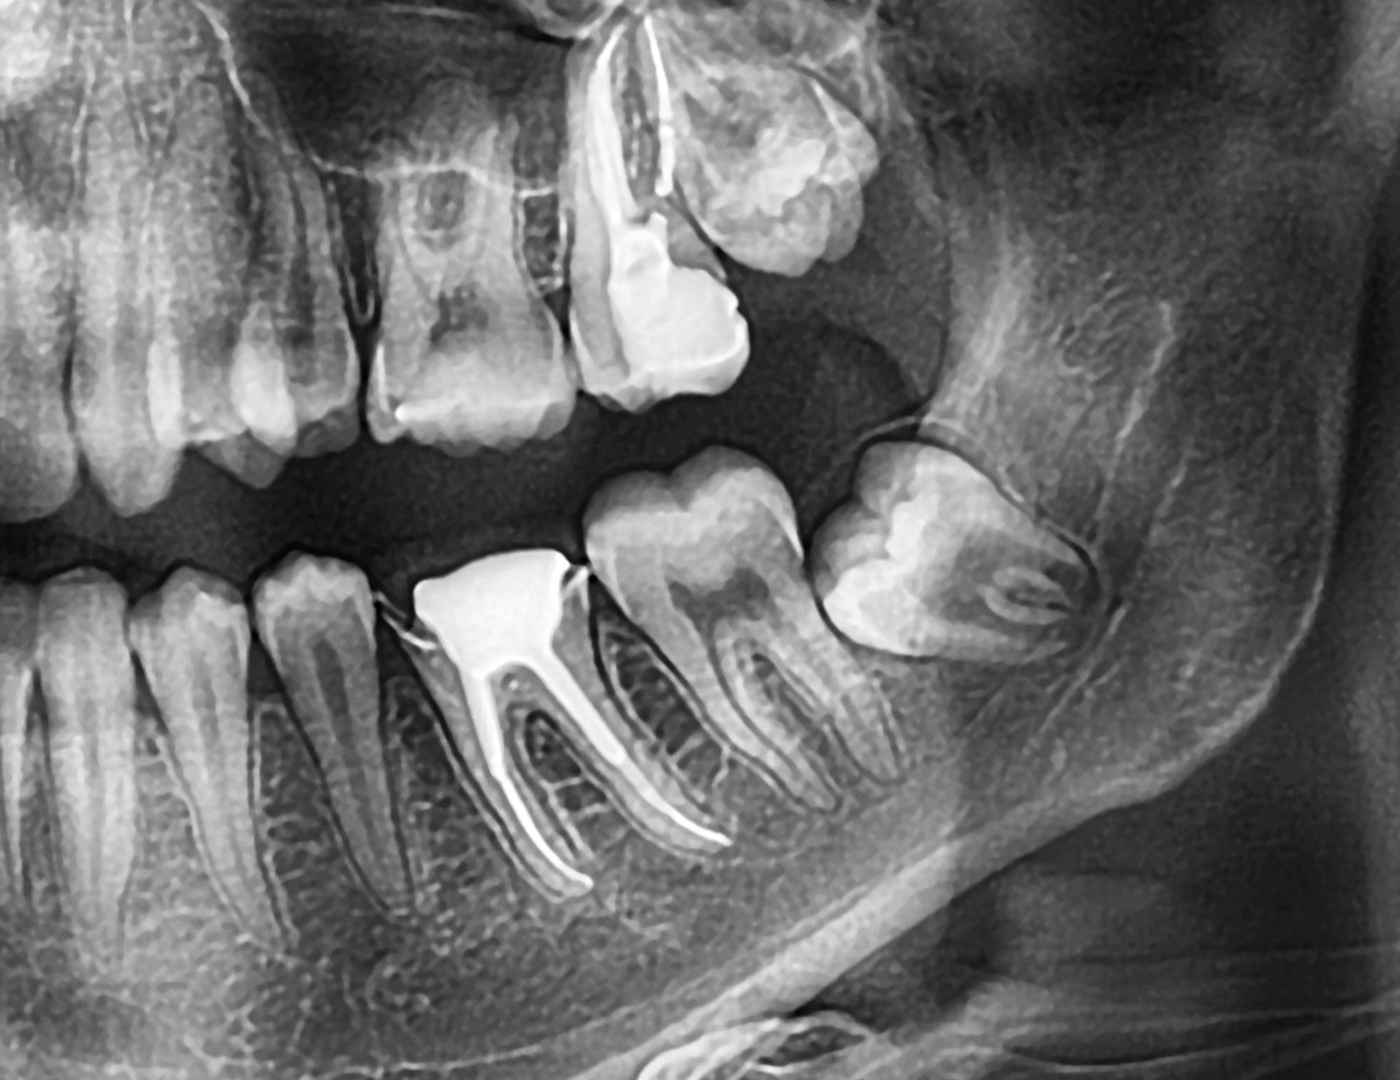

Wisdom teeth, also known as third molars, usually start to emerge in late adolescence or early adulthood. They are often removed because they can cause various oral health issues, such as impaction, crowding, pain, and infection. The extraction process typically involves making an incision in the gum, removing any bone that blocks access to the tooth, dividing the tooth into sections, if necessary, and finally, removing it.

7. Sinus Opening: Impacted wisdom teeth near your sinuses can potentially lead to sinus communication. In such cases, an opening forms between a tooth socket and a sinus. This risk can be eliminated by removing the last set of molars early. If it occurs, the opening should spontaneously close on its own. Avoid blowing your nose for a couple of days following the procedure to aid the healing process.